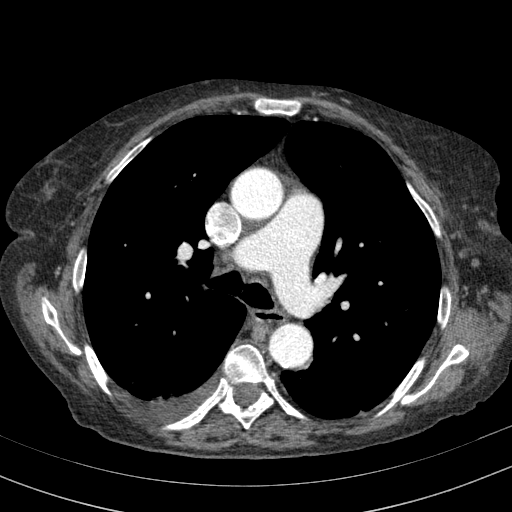

Generated VENOUS CT scan (A→B translation)

Full window (WL 1023.5, WW 4095 β†’ Low βˆ’1024, High +3071)

Actual HU range: [-1024.0, 847.3]